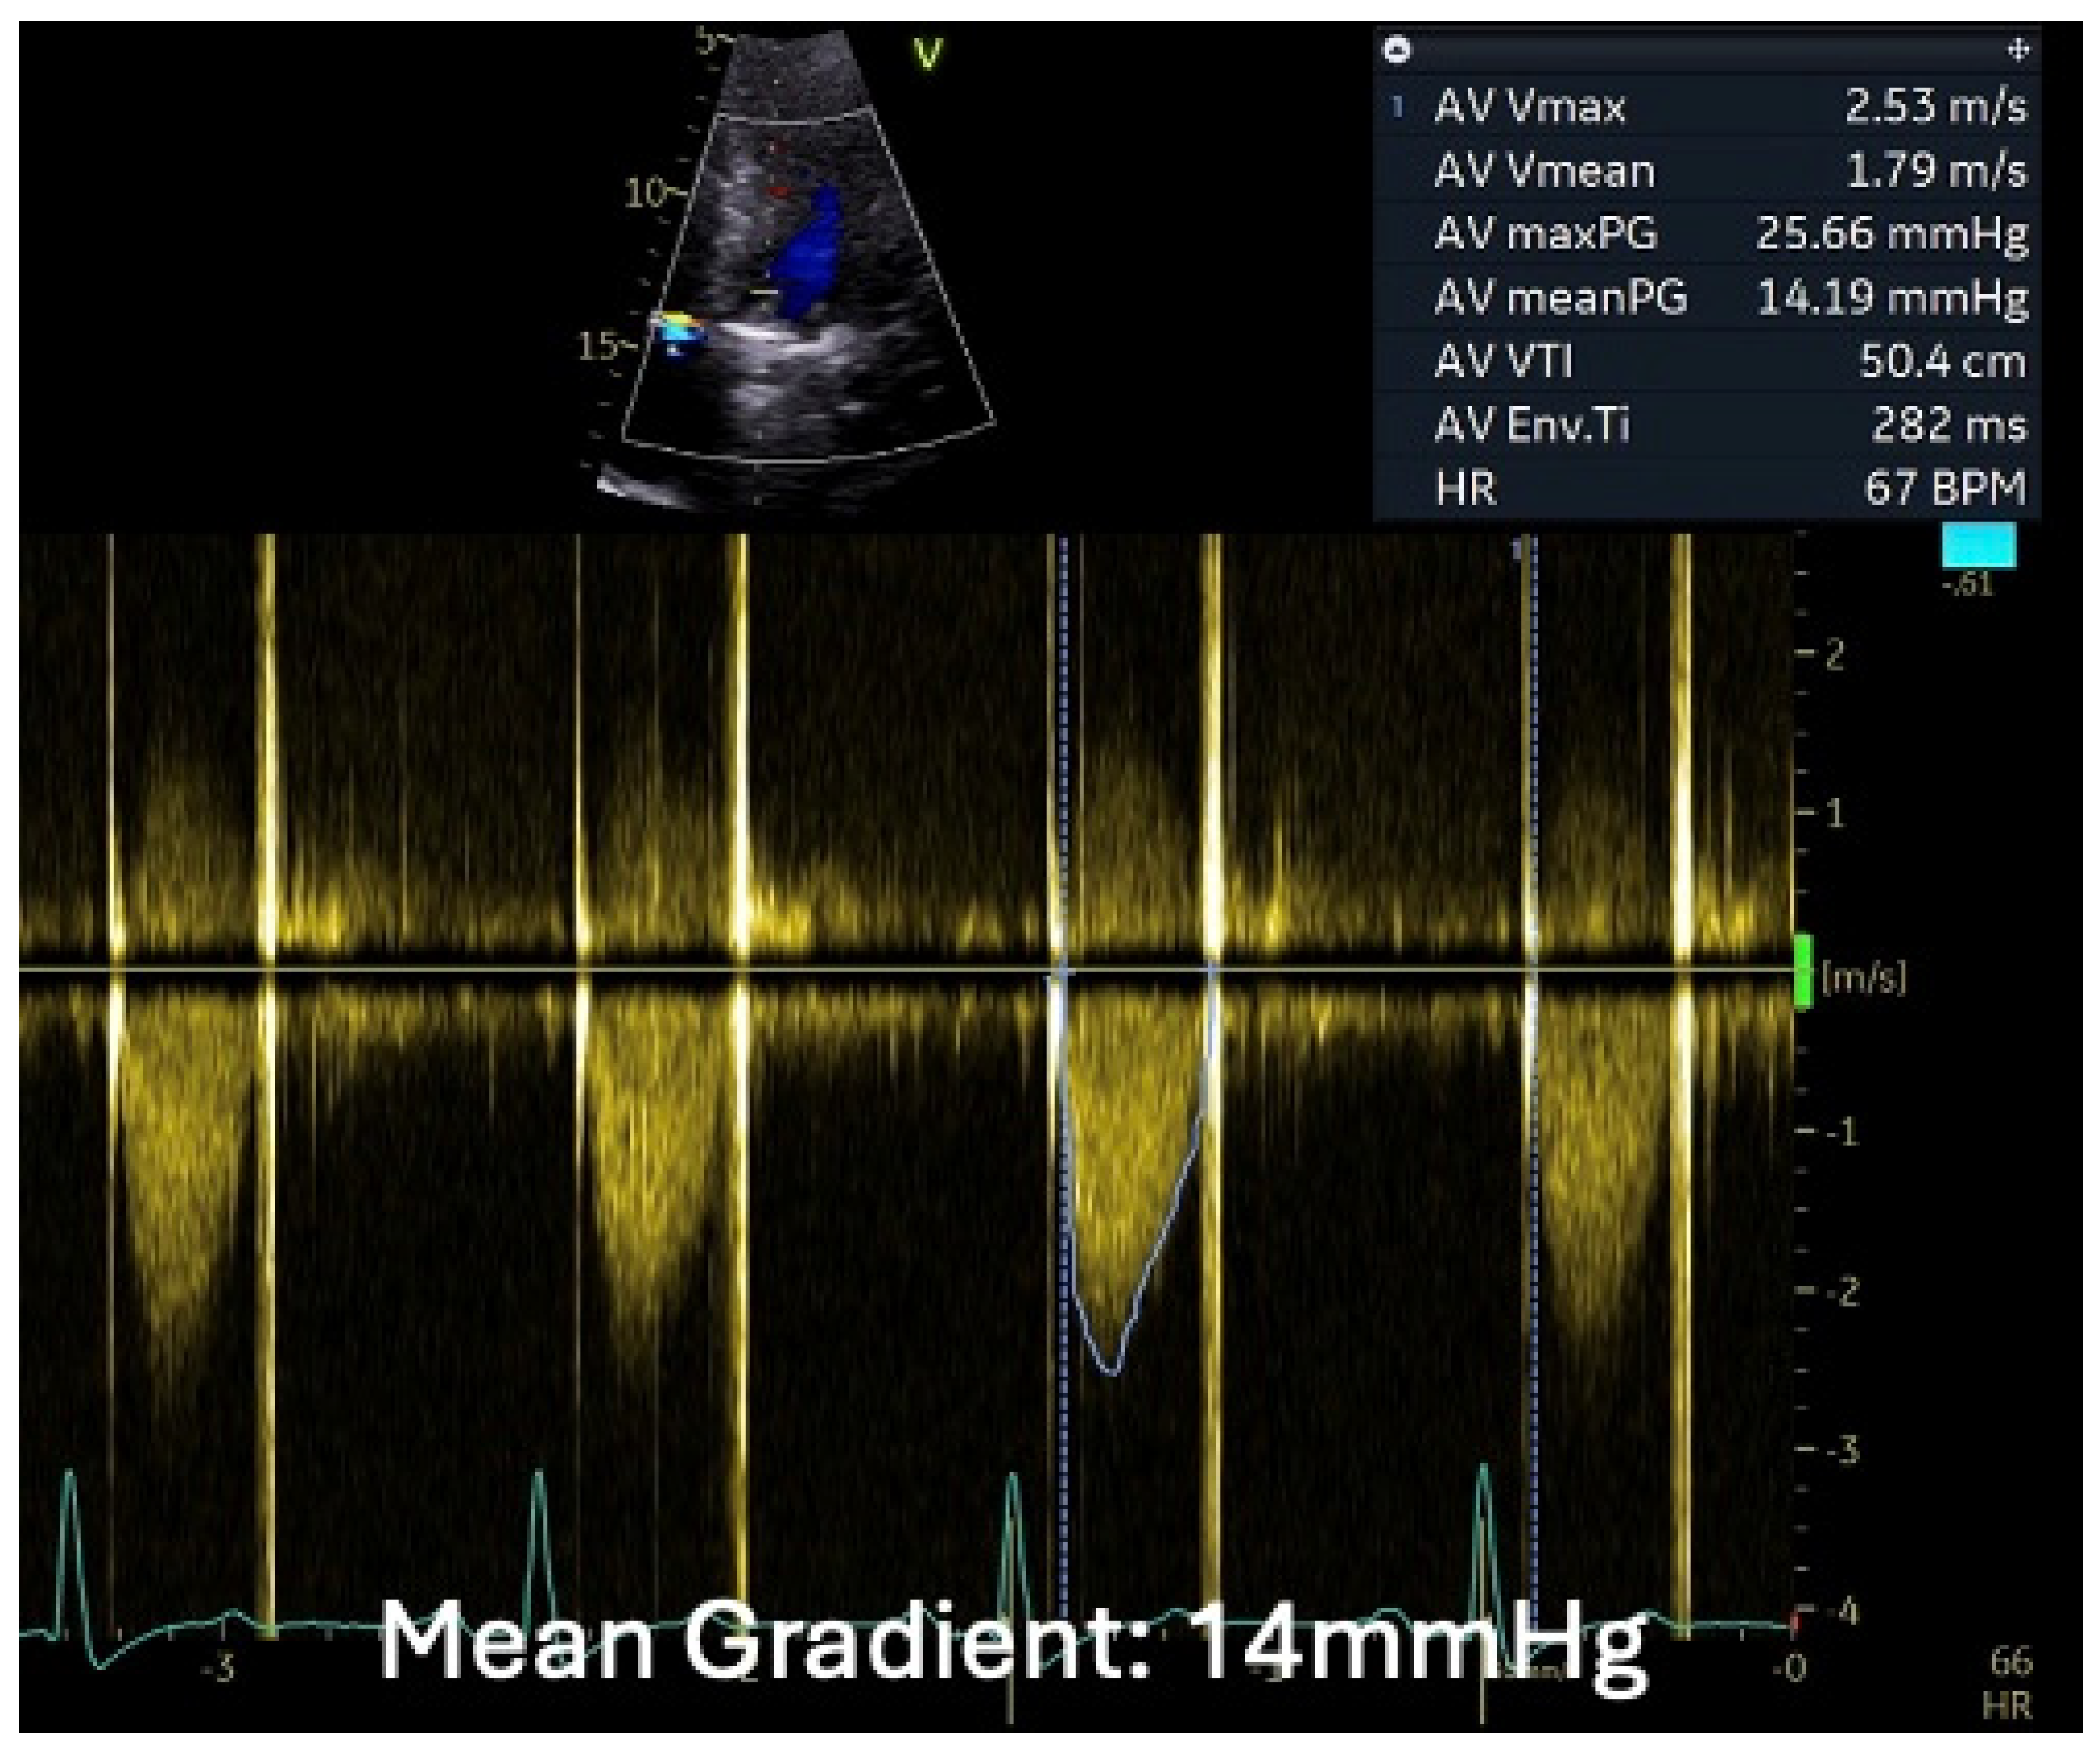

1.1.4. Case 4